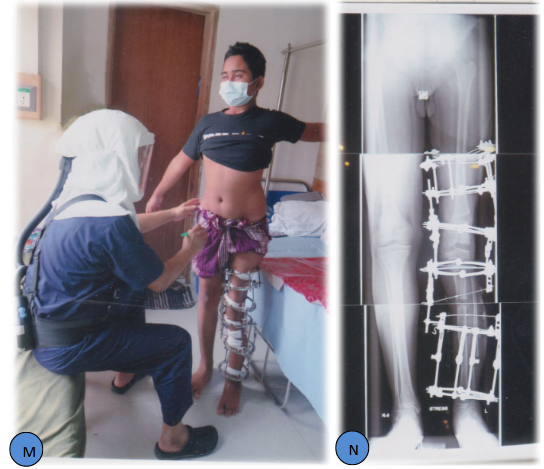

Citation: Bari MM, Shahidul I, Tanvir A, et al. Post traumatic genu valgum with valgus deformity of left lower femur and upper tibia valgus and procurvatum deformity with 10cm L. L. D and puckering of skin around knee with bad scar. MOJ Orthop Rheumatol. 2021;13(3):43-46. DOI: 10.15406/mojor.2021.13.00546

Post-traumatic femoral valgus and upper tibia valgus and procurvatum deformity with 10cm LLD were corrected with Ilizarov Technique. The lower femur deformity correction and deformity correction of upper tibia and lengthening were carried out simultaneously. This case demonstrates an approach to large complex post-traumatic deformity in the left knee region with puckering of the skin and bad scar.

A 14 years old boy sustained motor vehicle injury in the left inferior extremity at the age of 8. He was treated at Combined Military Hospital, Dhaka at that time because father is an Army personnel. Now, he was referred to Bari-Ilizarov Orthopaedic Centre for further management, that is for correction of deformity and L. L. D. Plain X-ray and clinical ndings showed his left lower extremity with distal femur valgus deformity, proximal tibia valgus and procurvatum deformity. He was complaining left knee pain and his gait was awkward. His father was anxious regarding his deformity correction and lengthening of left lower limb.1–5

Figure 1 A-J 14 years old boy, Post Traumatic Genu Valgum with Valgus Deformity of left Lower Femur and Upper Tibia Valgus and Procurvatum Deformity with 10cm L. L. D and Puckering of Skin around Knee with Bad Scar.

Figure 1 K-T